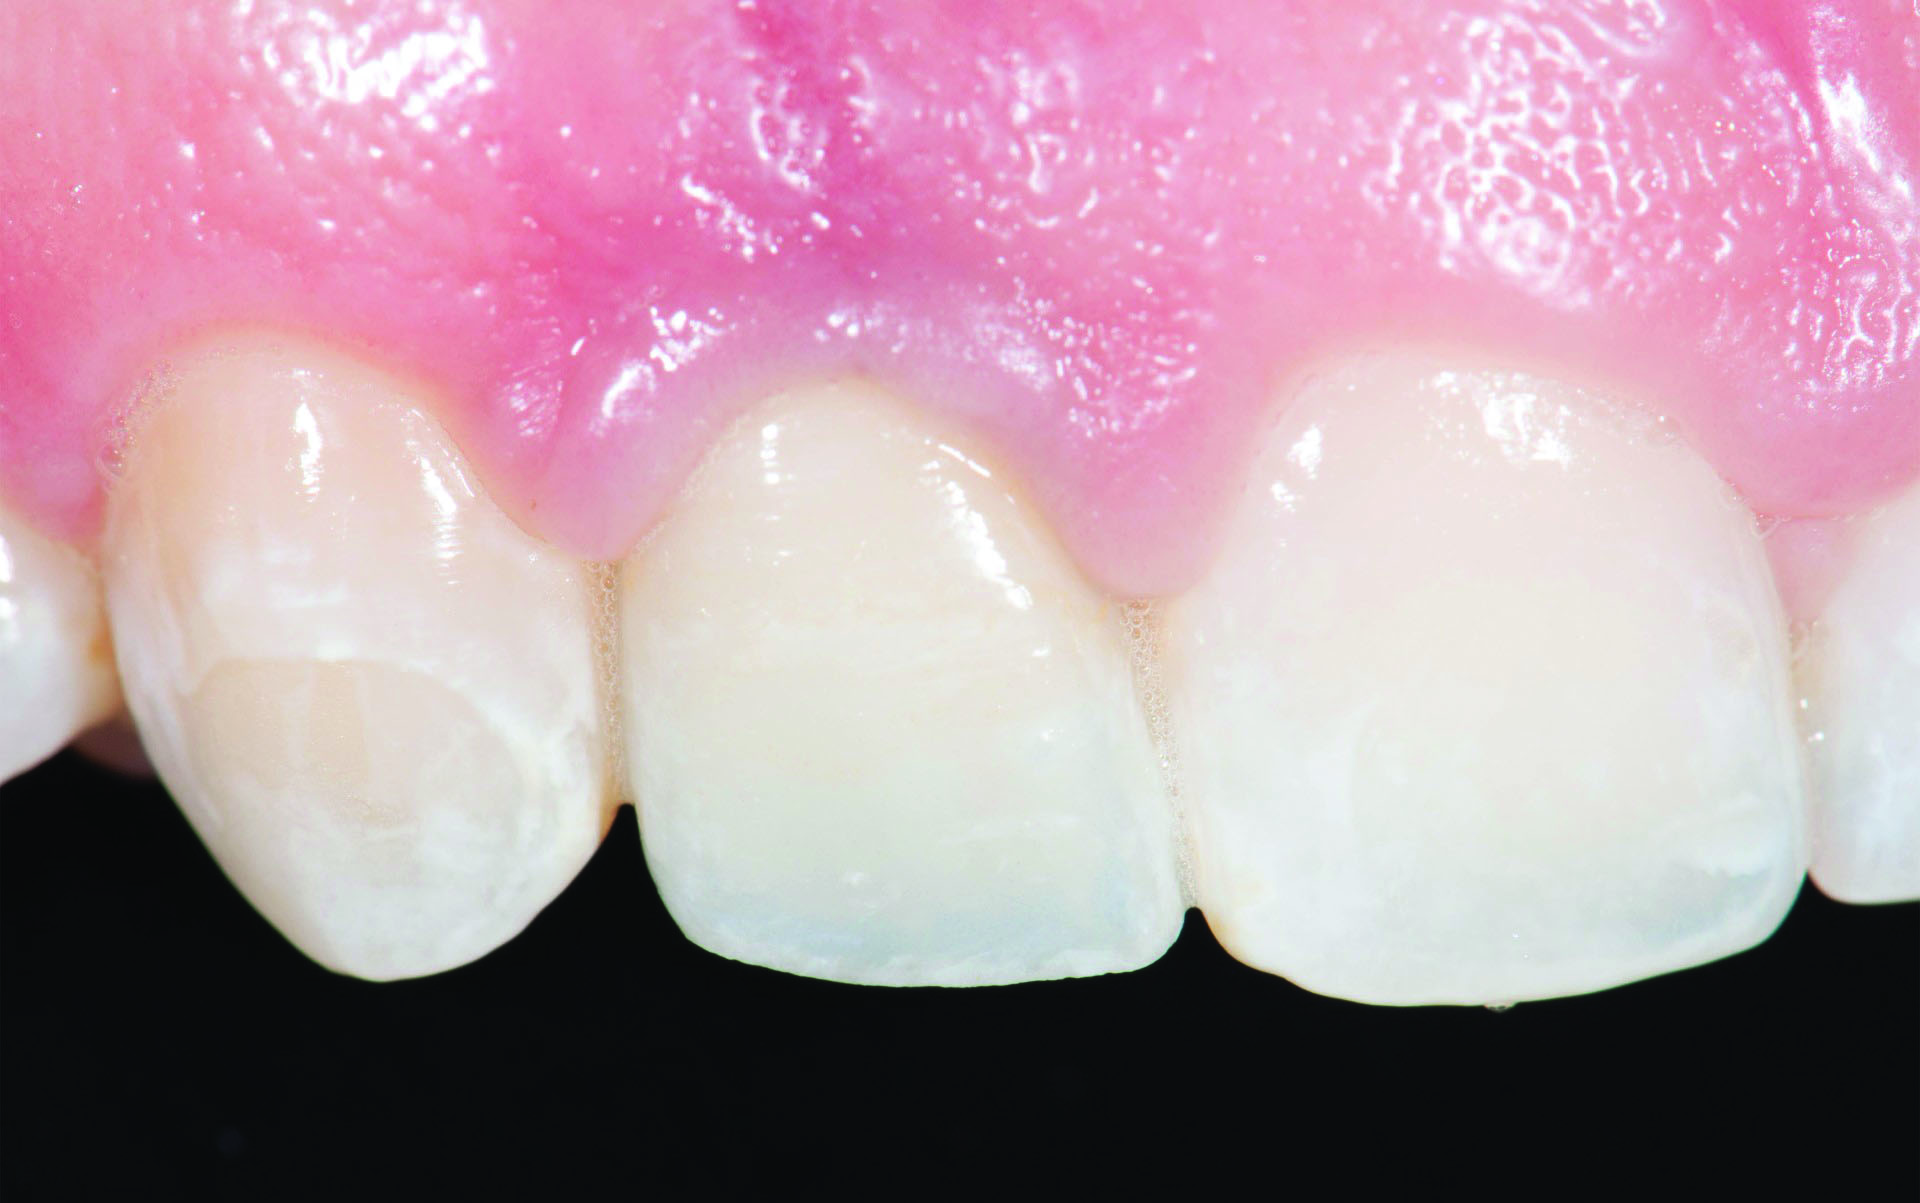

Of those respondents who chose to use a cement-retained crown, 33% would employ custom titanium abutments (Figure 1, C) while 42% would use zirconia abutments with a titanium base (Figure 1, D).1 A clinical concern with cement-retained restorations is the show-through of the titanium abutment through the crown ceramic or soft tissue. When using a zirconia abutment with a titanium base this issue is mostly negated, because the zirconia abutment shade can be selected to match the restoration or surrounding teeth preparations (Figure 1, D). With regard to soft tissue, the zirconia portion of the abutment below the soft tissue has been reported to provide a more esthetic result than titanium,3 as titanium may cause soft tissue to appear dark, especially in patients with a thin gingival biotype. Additionally, the collar of the titanium base in such a restoration can be as thin as 0.7 mm and, therefore, have no negative influence on bone stability4 while enabling the titanium base to be essentially hidden within the sulcus.

Fig 5. Set-up for performing anodization of a titanium abutment. The source of the direct current in this instance is a DC power supply (left). Once connected to the positive terminal (encased in red cable), the dental implant abutment is submerged in an electrolytic solution.

Figure 5